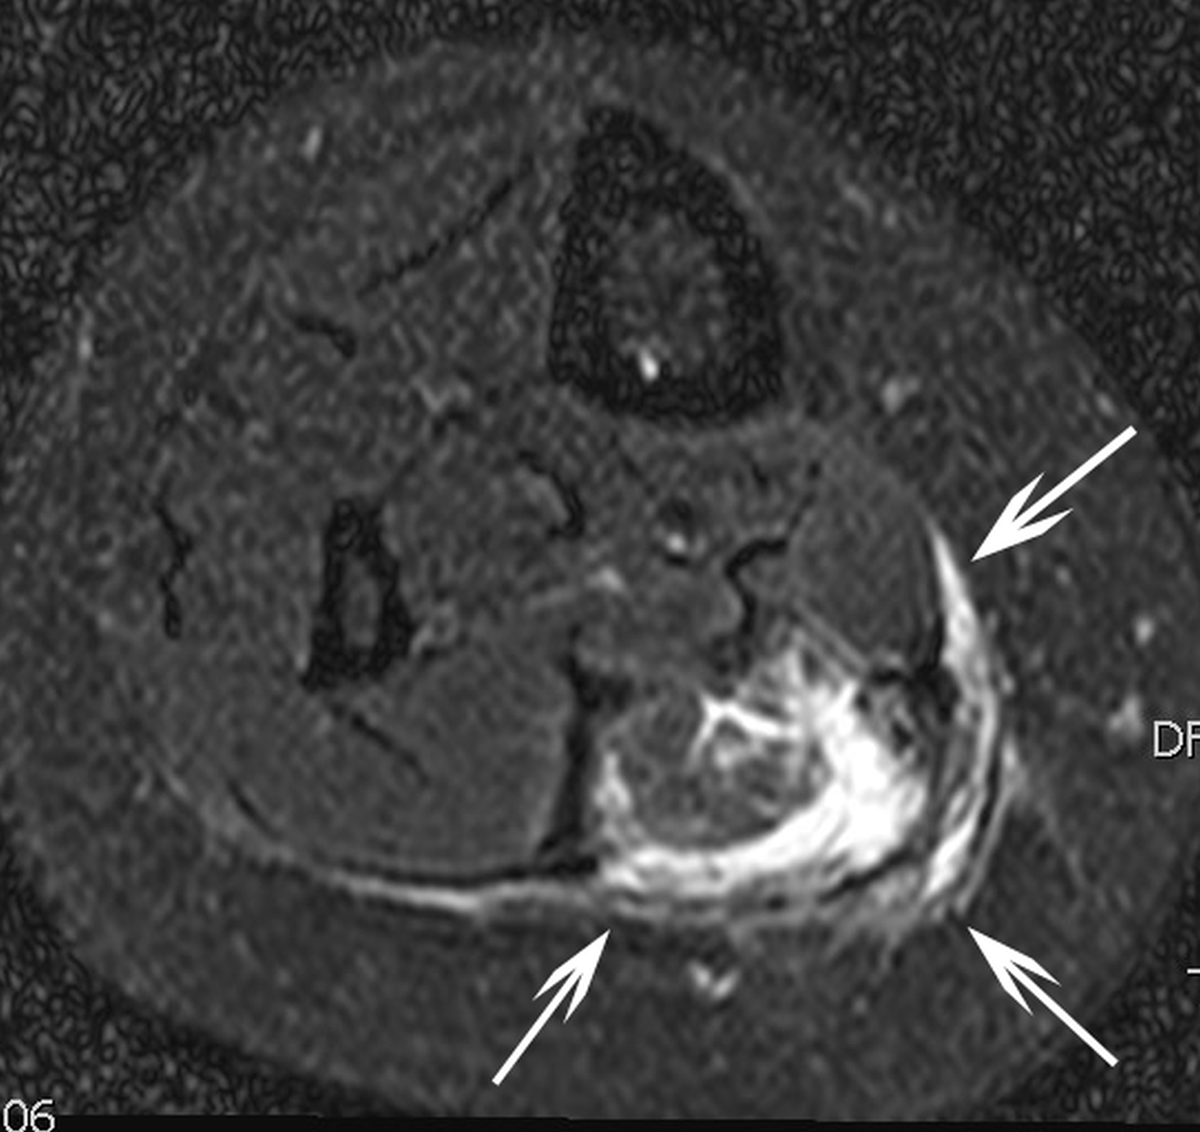

Figure 1b

T2-weigthed axial magnetic resonance image in the same patient three months after percutaneous radiofrequency ablation which was performed after two failed percutaneous sclerotherapies with sotradecol. Hyperintense rim (white arrows) around the ablated area suggestive for perileasional oedema.